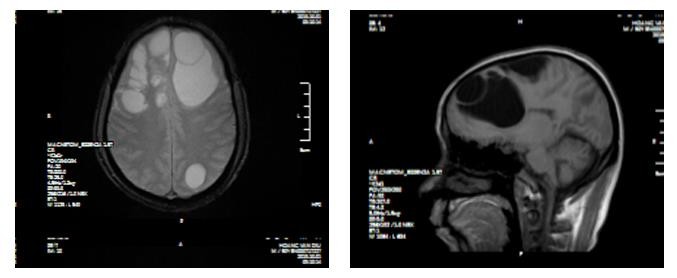

Tại Bệnh viện đa khoa tỉnh Phú Thọ, người bệnh được chỉ định chụp CT sọ não, kết quả cho thấy ổ sán não khổng lồ ở cả hai bán cầu trái và phù não diện rộng. Bệnh nhân được chỉ định can thiệp ngoại khoa.

Cả ổ sán trong não người đàn ông được các BS phẫu thuật lấy ra.

Các bác sĩ khoa Ngoại thần kinh - Bệnh viện đa khoa tỉnh Phú Thọ đã hội chẩn để tiến hành phẫu thuật cho người bệnh. Cuộc phẫu thuật kéo dài khoảng 2 giờ, ổ sán trong não đã được kíp phẫu thuật sử dụng các trang thiết bị hiện đại như kính hiển vi phẫu thuật, máy hút siêu âm cùng với kinh nghiệm chuyên môn đã lấy được chọn vẹn cả ổ nang sán..